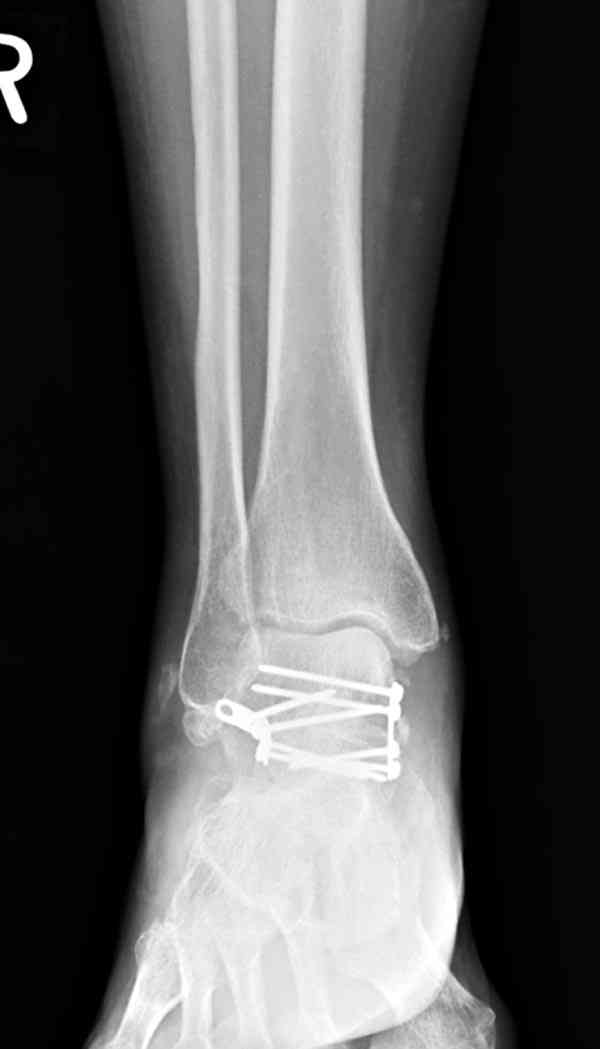

И второй случай из недавней ташкентской практики, (извините за качество ренгенограммы и только в одной проекции) случай падения с высоты (кстати моего друга - известного киноактера) - открытый

смещенный перелом тарана, с переломом переднего края дистального эпиметафиза большеберцовой кости.

При поступлении в приемной сделана первичная обработка с ушиванием открытой латеральной раны и вытяжением за пятку.

Из-за отсутствия времени пришлось оперировать на второе утро, из материала, что имеем на месте, фиксирован двумя шурупами, а третий-это контур сломанного жойстика в 4 мм. На дистальный медиальный конец тибиа antiglide 3.5 мм пластина. Через пару дней выписан и несмотря на предупреждение, самостоятельно начал нагрузку в 4 недели, время не ждет, снимается в боевике в Росийской Федерации.